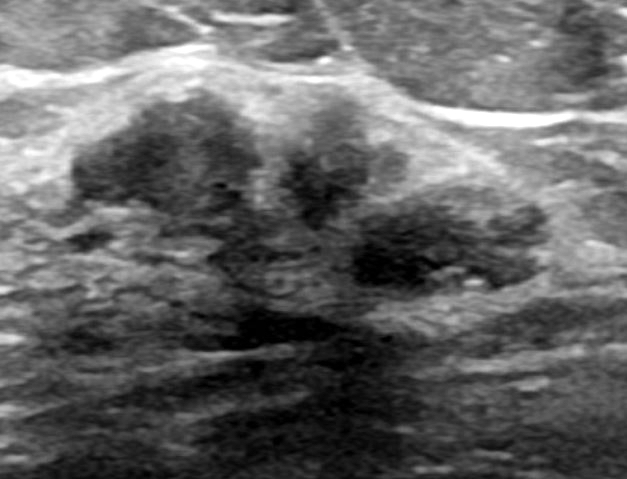

- Well circumscribed, homogenous, hyperdense or isodense, solid mass (Clin Imaging 2018;51:300)

- Typically devoid of calcifications

- Hypoechoic on ultrasound, may have posterior enhancement

- May be multilobulated

- Bilateral and multicentric tumors rare (Mod Pathol 1996;9:786, Int J Surg Pathol 2018;26:242)

Radiology images